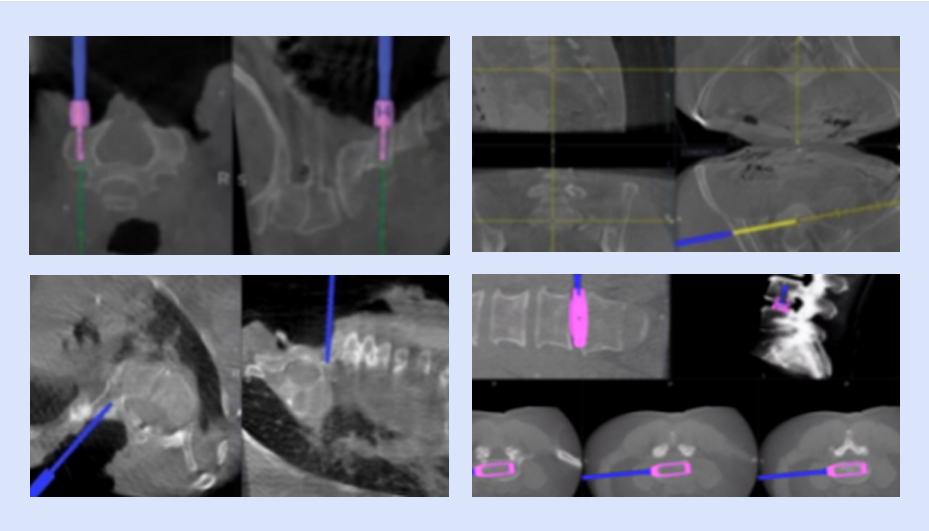

以脊柱療法為中心的可視化賦能

全流程可視

可視化置釘

可視化椎間融合

具備全套導航專用椎間融合工具,實現從椎間隙定位、放置通道、椎間處理、試模、放置融合器的全程可視化,提高手術效率,做到精準融合。